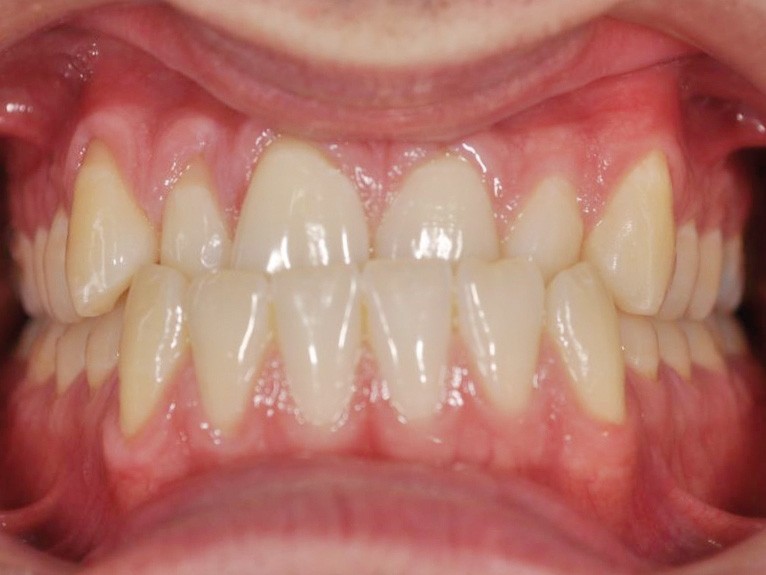

L’examen de la face montre un visage avec un équilibre des étages moyen et inférieur, une petite lèvre supérieure (fig. 1) et un sourire étroit et inesthétique du fait de l’articulé inversé antérieur (fig. 2).

L’examen fonctionnel révèle une propulsion de la mandibule en fin d’occlusion.